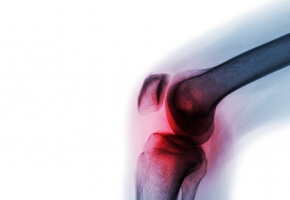

Cette technique, essentiellement utilisée dans le cas des douleurs neuropathiques, consiste à contre-stimuler le système nerveux en périphérie afin d’induire un effet antalgique. Une étude multicentrique a analysé son effet sur l’arthrose avec un système miniaturisé de stimulation électrique appliqué au niveau du genou de patients. Contre toute attente, un effet antalgique chez ceux-ci a été démontré. C’est une étude très encourageante car c’est un système maniable par les patients dont l’effet est supérieur aux opioïdes faibles et qui n’a pas d’effets indésirables.